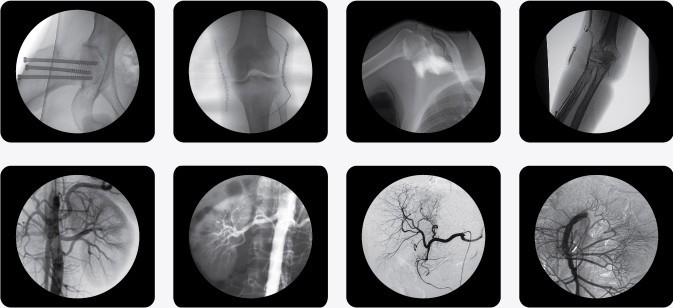

眾所周知,放射科設備在醫(yī)院中有著重要地位,它可以幫助醫(yī)生看到人體內(nèi)部結(jié)構。隨著科技的發(fā)展,C型臂的使用越來越廣泛了,移動式C型臂X光機被稱為為可移動的C形臂的X光機,又叫C臂X光機、C臂機、百萬像素C型臂、C臂、小C臂、小C、骨科C臂等。主要用途有:1、骨科:整骨、復位、打釘;2、外科:取體內(nèi)異物、心導管、植入起搏器、部分介入治療、部分造影術及局部攝影等工作;3、其他:配合臭氧機治療疼痛,小針刀治療,婦科輸卵管導引手術等。

以下是南京C型臂X光機PLX7000C的產(chǎn)品參考圖,點擊產(chǎn)品圖下方紅色的產(chǎn)品名稱可以直接進入詳情頁面:

(普朗品牌產(chǎn)品--C型臂X光機PLX7000C